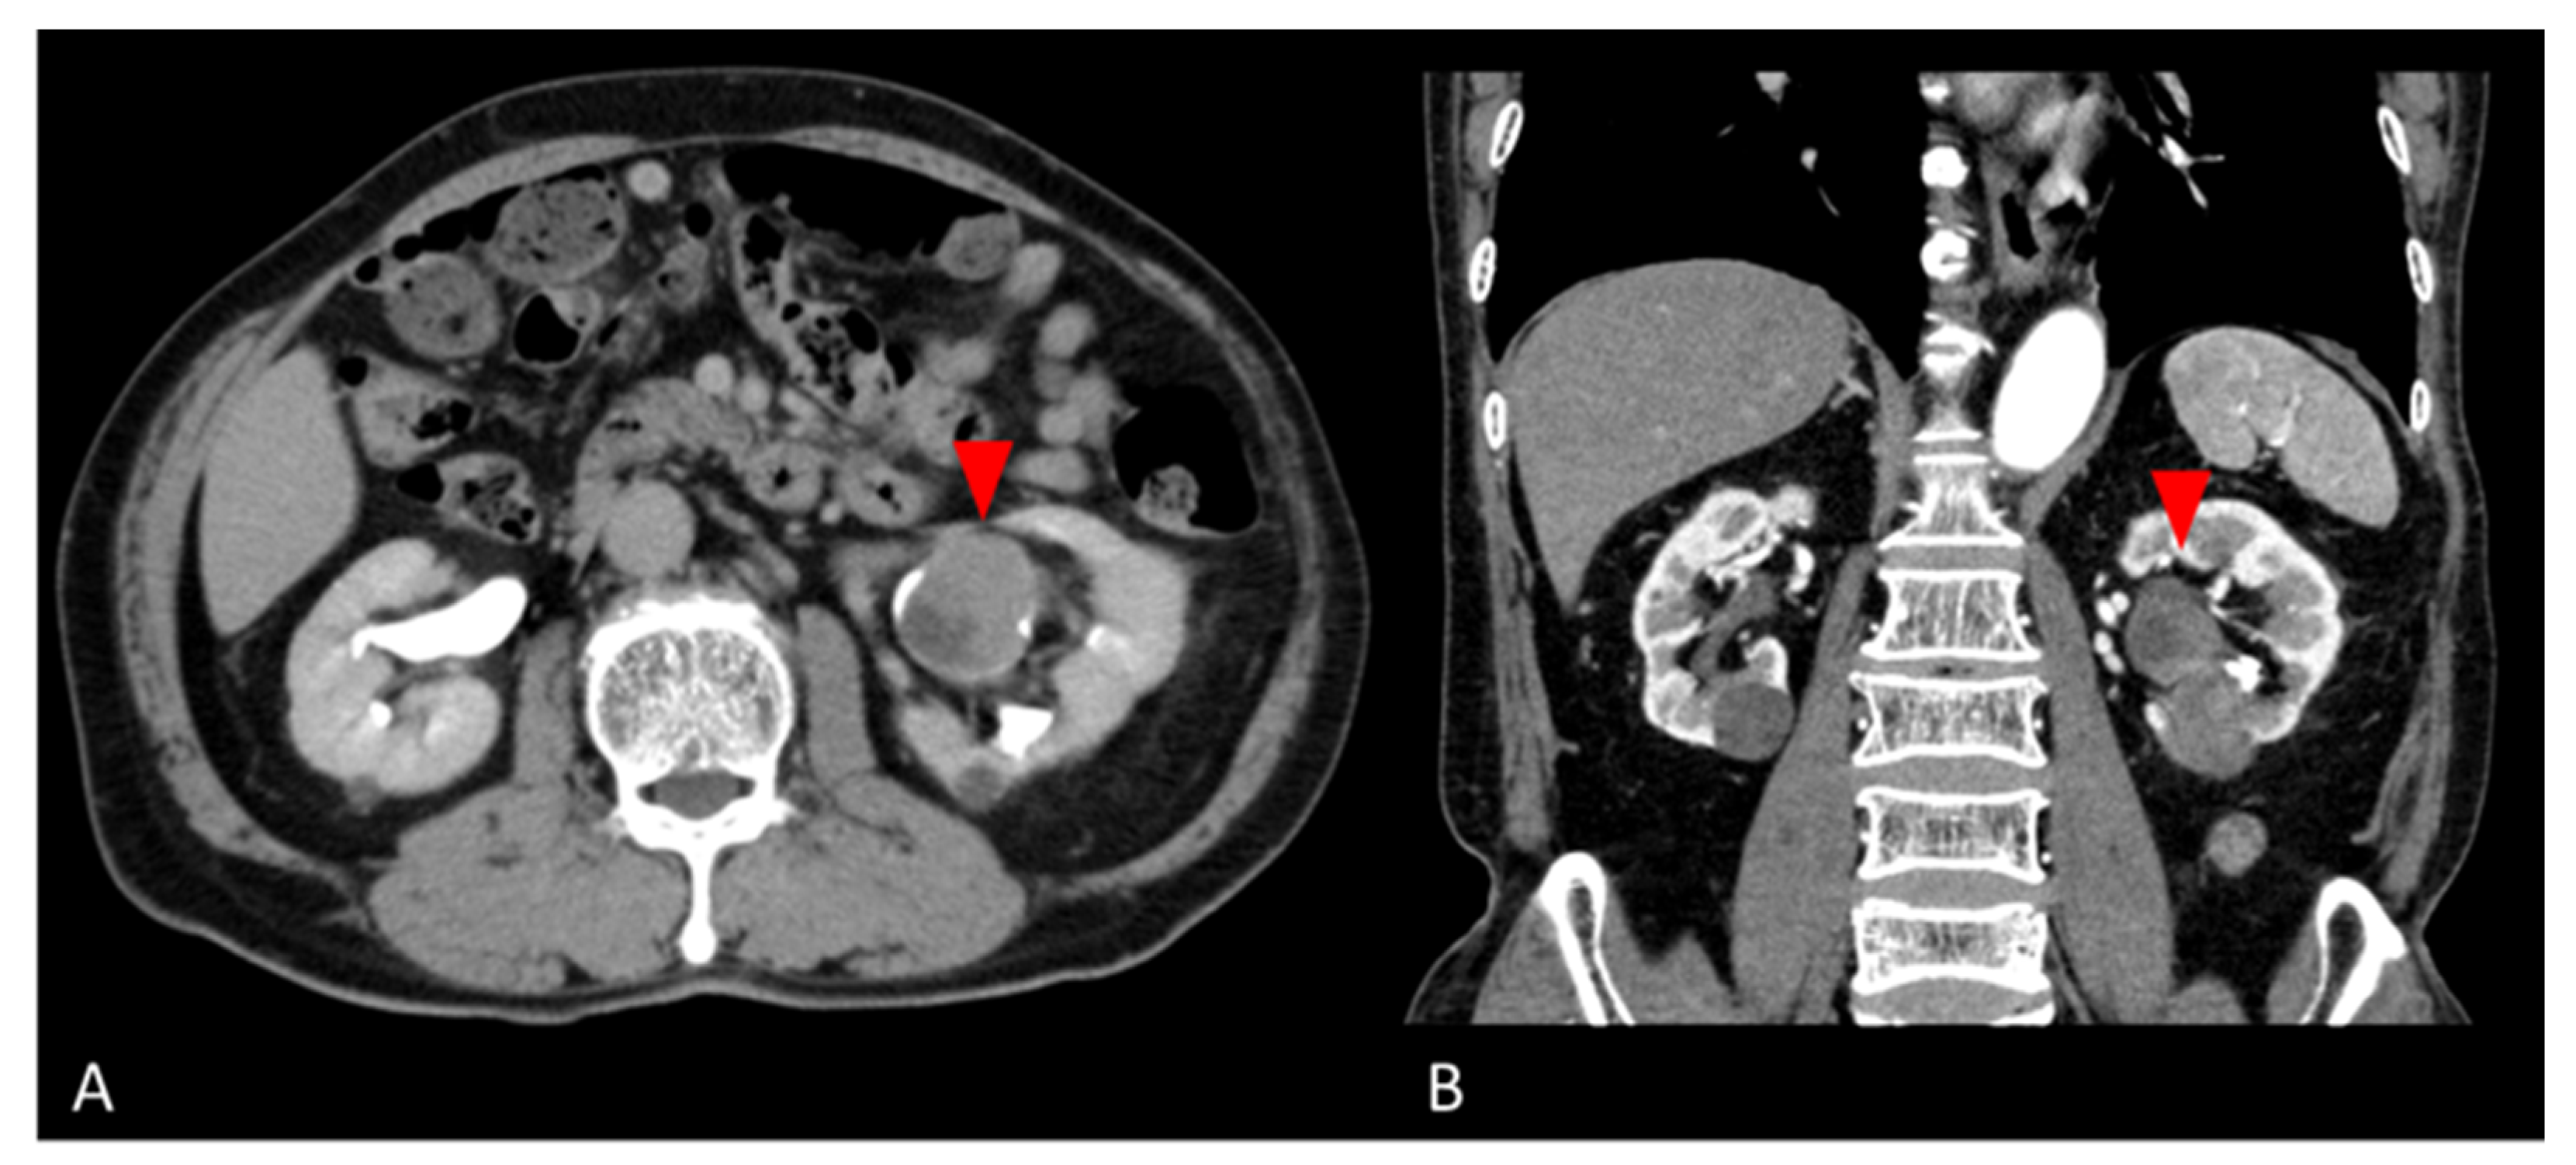

2. Case Presentation

2.1. Clinical Summary